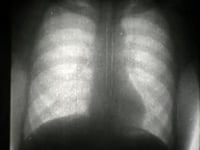

Röntgenfilm II / X-Ray Film II

Röntgenfilm II - Herztätigkeit und Atmung beim Menschen X-Ray Film II - Heart and Breathing Reichsstelle für den Unterrichtsfilm 1936 - 6 minutes Der Film ...

2009-05-10 05:19 5,725 Vimeo